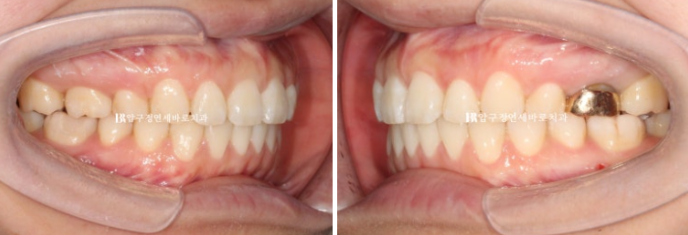

Now the midline is aligned,

25.01

and the molar bite is also good.

23.06~25.01